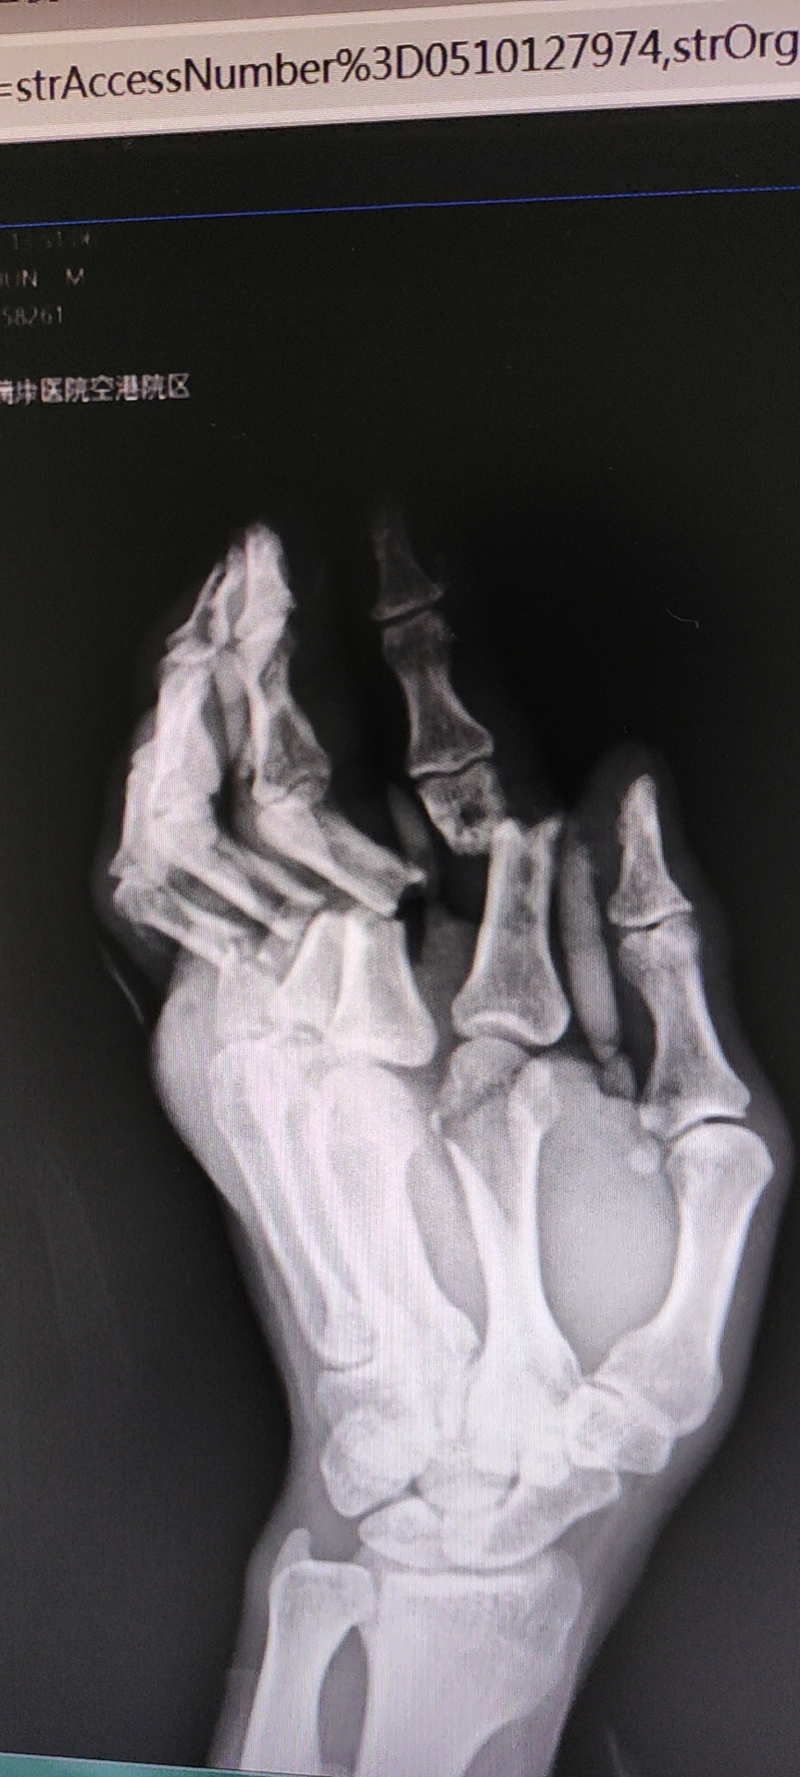

据了解,患者老A(化名)在工作中被重物砸伤,致左手食指、中指、无名指、小拇指等四根手指骨折并伴血管神经损伤,病情危急,接诊的基层医院无救治条件,于是建议老A紧急转到广西中医药大学附属瑞康医院。时间不等人,两地医院通过联动转诊,紧急通过急诊绿色通道送至南宁市。

到达我院后,急诊科组织了会诊,修复重建显微外科值班医生张卫华处置评估后,建议给老A进行紧急手术处理。“老A虽然左手虽然被厚厚的纱布包裹,但情况比较严重,仍有血液不断渗出,手指末端已出现血液运输障碍”张卫华医生跟老A家属沟通,“老A受伤已超过两个小时,而且就诊途中遇到颠簸辗转,他已处于极度虚弱状态,需要马上进行手术”。

术前